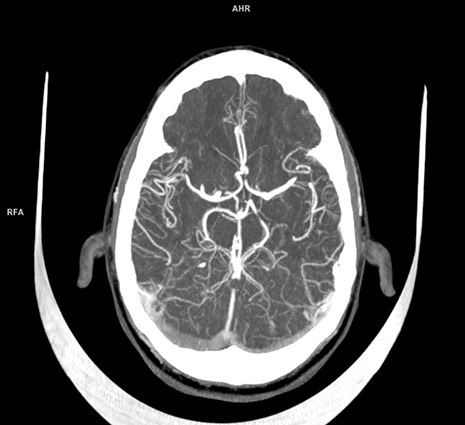

TIMEDOO肽度(微信號:Time-doo)獲悉,西門子醫(yī)療保健公司獲得FDA批準(zhǔn)該公司的Somatom On.site移動式頭部CT掃描儀。該設(shè)備可以很輕易地直接帶入病房,這要?dú)w功于它的動力車輪和車載電池。

檢查結(jié)束后,掃描片子會自動傳遞到醫(yī)院的放射圖像數(shù)據(jù)庫,放射科醫(yī)生可以立即對其進(jìn)行閱片。

西門子醫(yī)療保健北美公司計(jì)算機(jī)斷層掃描副總裁道格拉斯·瑞安在聲明中說:“Somatom On.site改變了需要CT頭部掃描的危重病人的護(hù)理服務(wù)流程?!痹撓到y(tǒng)可提供ICU、神經(jīng)科和放射科的醫(yī)療保健專業(yè)人員所要求的可靠和一致的圖像質(zhì)量。此外,床邊成像有助于減少運(yùn)送病人的次數(shù),從而降低感染風(fēng)險(xiǎn),同時(shí)提高勞動力效率?!?/p>